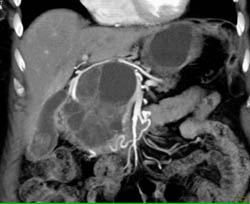

Cystadenoma